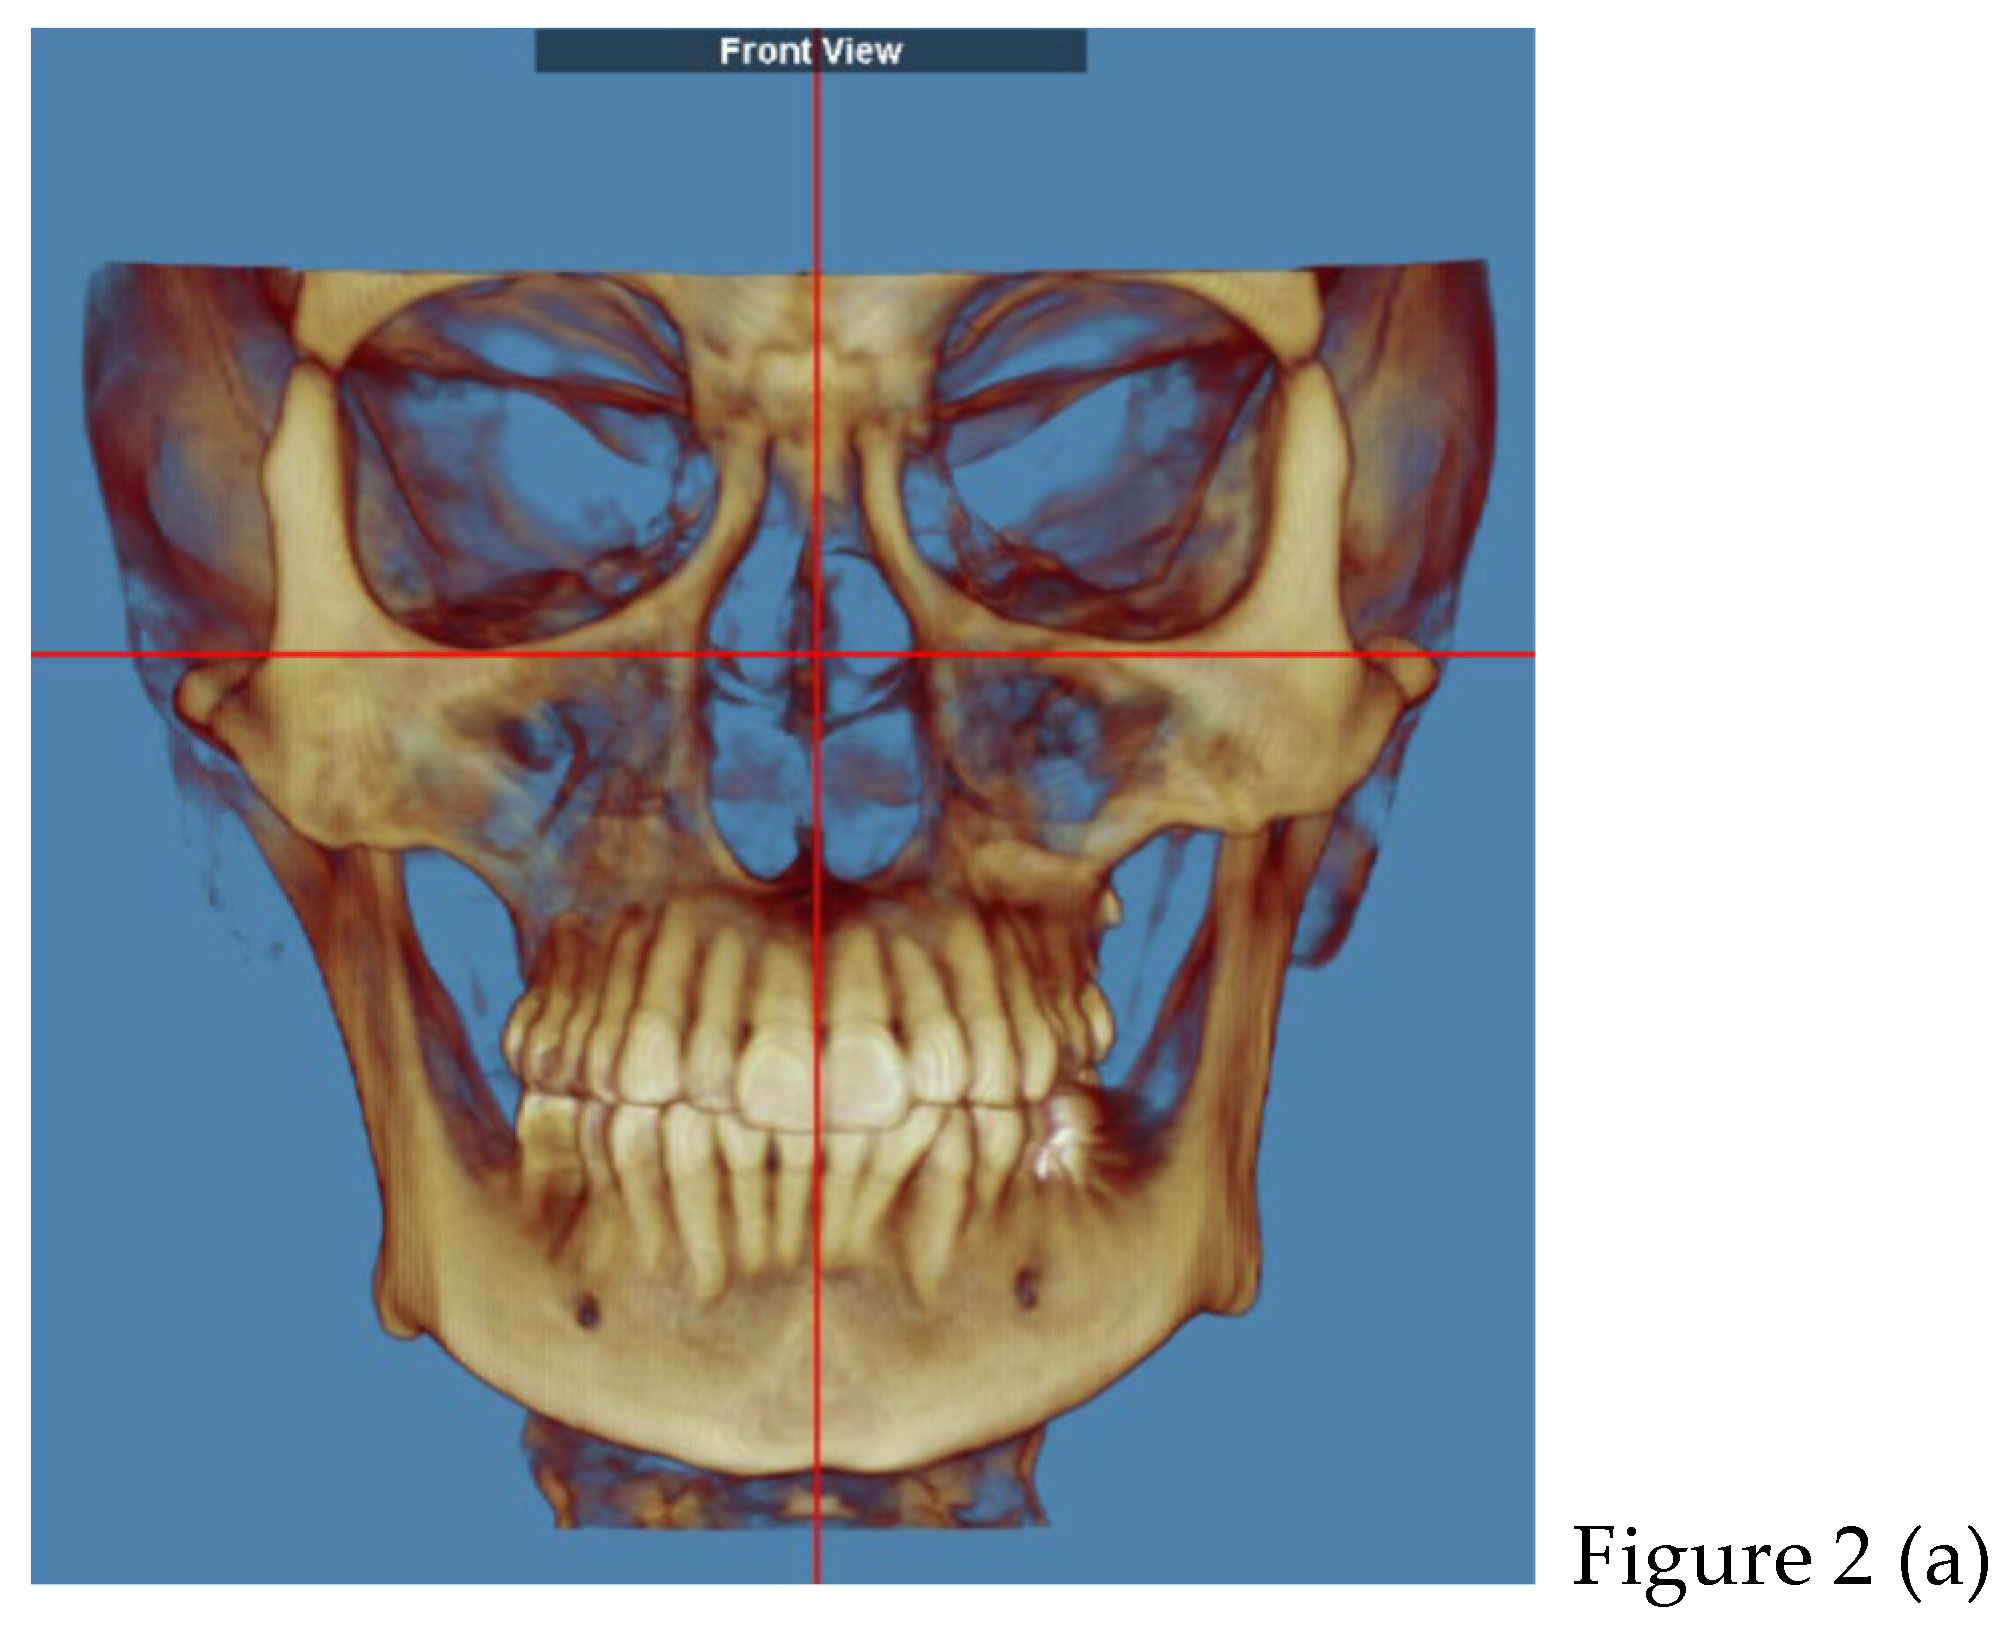

2.2. Cone Beam CT Analysis

| CBCT (t0) | |